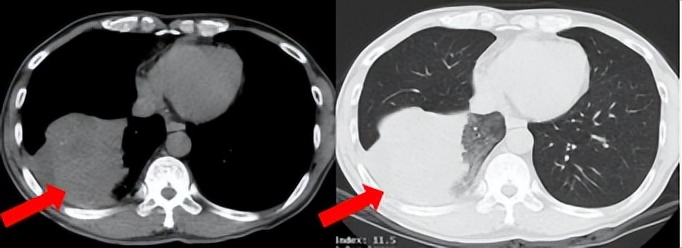

55岁男性,无吸烟史,有饮酒嗜好。2024年11月常规体检胸CT:左肺上叶占位性病变,大小约2.7×2.4cm,恶性可能大;左肺、左侧叶间胸膜及胸膜下多发微小结节,转移待除外。左侧胸腔积液,部分骨质改变。2024年12月初肺穿刺活检,病理:(肺)腺癌。NGS基因检测:CCDC6-RET(exon1-exon12)融合突变阳性(丰度:13.21%)。PD-L1表达阳性(TPS=35%,CPS=45)。

治疗经过:2025.01开始口服普拉替尼(400mg,qd)。2025.03复查胸CT:左肺上叶、右肺上叶、左肺斜裂见多发实性结节影,长径范围约3-17mm,较大者大小约17mm×12mm,位于左肺上叶下舌段,可见分叶、毛刺、胸膜凹陷、棘状突起征象。纵隔内小淋巴结。评效PR,随访中。治疗期间未出现毒性反应。

2024.12

2025.03评效PR